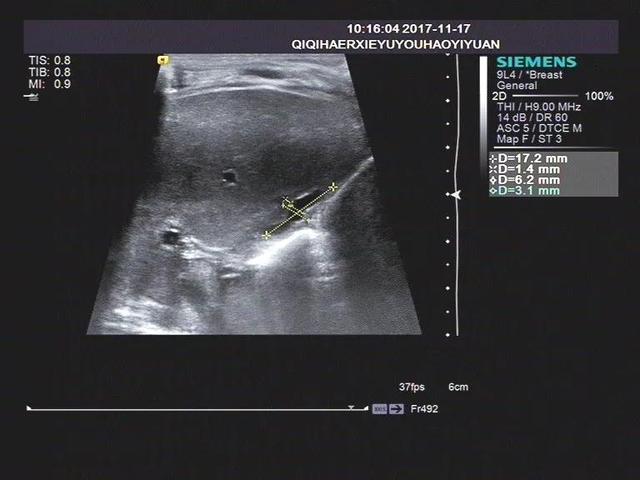

案例1

胆囊的声像图特征主要是:饥饿和餐后状态(建议喂奶后0.5小时观察,1小时多次观察),胆囊形态较小或假腔仅为狭缝状液体暗区。胆囊切面形态异常不规则,壁粗糙僵硬,部分病例可见双侧回声,进食后胆囊大小不变。

1)胆囊大小正常,但形状僵硬,边缘不自然。长度可达2厘米左右,内径大于0.4厘米,可有小的憩室样结构,部分形似香肠。

2)胆囊小,长度小于1.0 ~ 1.5厘米,内径0.2厘米,充盈不良。

3)胆囊小而不饱满,只能看到胆囊印痕。